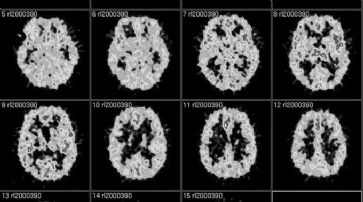

Mailand - Eine Forschergruppe am IRCSS Ospedale San Raffaele hat ein innovatives Paradigma zur Untersuchung der für die Träume verantwortlichen Hirnregion entwickelt.

Damit eröffnen sich neue Ansätze zum Verständnis von pathologischen Störungen wie Psychosen und Depressionen. Zur Durchführung der wissenschaftlichen Arbeit benutzt wurde das Verfahren der funktionellen Magnetresonanztomografie. Ersponnenes nacherzählen

«Dabei haben wir die für Kreativität und Vorstellungsvermögen zuständige Hirnrinde der rechten Hemisphäre unter die Lupe genommen», erklärt Projektleiter Francesco Benedetti.

Die Entdeckung der italienischen Wissenschaftler besteht darin, dass diese Region nur dann aktiviert wird, wenn die Probanden ihre Fantasien mitteilen. Bei der Wiedergabe der Träume hingegen wird diese Region schrittweise deaktiviert - mit der Folge, dass diese anschliessend auch im Wachzustand zusammenhanglos und kaum verständlich bleiben.

«Wir haben deshalb Grund zur Annahme, dass diese temporären Strukturen sowohl für den Erhalt einer hohen logischen Folgerichtigkeit bei den Fantasien im Wachzustand als auch für deren graduelles Verschwinden in der Traumphase verantwortlich sind», bestätigt der Experte. Es handle sich um einen wichtigen Fortschritt auf dem Gebiet der Neurowissenschaften.